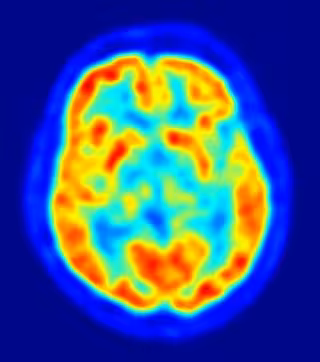

Neurocientíficos de la Universidad de Nueva York han identificado las partes del cerebro que utilizamos para recordar la sucesión de eventos dentro de un episodio. El estudio, que aparece en el último número de la revista 'Science', mejora nuestra comprensión de cómo se procesan los recuerdos y ofrece una guía básica para hacer frente a potenciales trastornos relacionados con la memoria.

Investigaciones anteriores han demostrado que el lóbulo temporal medio del cerebro (MTL) tiene un papel importante en la memoria declarativa, es decir, la memoria de hechos o sucesos, y que los daños en esta área causan un deterioro de la memoria. Más específicamente, la memoria declarativa se encuentra alterada en los pacientes que sufren Alzheimer. Sin embargo, poco se sabe acerca de cómo las estructuras individuales dentro de la MTL recuerdan información sobre cuándo ocurrió un suceso específico, como, por ejemplo, el orden de los brindis en una boda.

Sus resultados mostraron que dos áreas principales del MTL están involucradas en la integración de "qué" y "cuándo": el hipocampo y la corteza perirrinal. El hipocampo, conocido por tener un papel importante en una variedad de tareas de la memoria, proporciona una señal de sincronización incremental entre los eventos clave, proporcionando información sobre el paso del tiempo desde el último evento, así como del tiempo estimado hasta el próximo. La corteza perirrinal integra la información sobre "qué" y "cuándo", qué ocurrió primero o segundo en una serie.